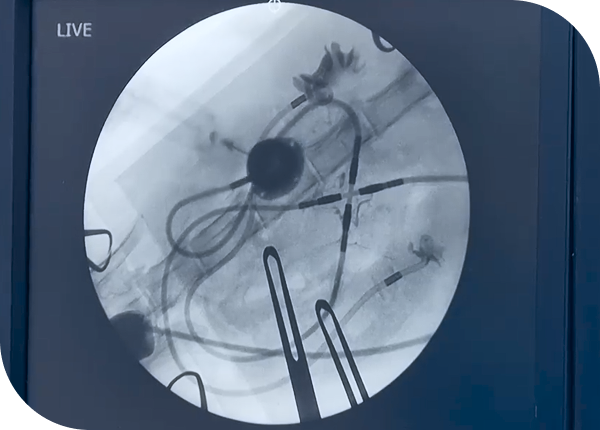

식도·기관·폐 등 움직이는 장기를 영상으로 관찰해 정적인 검사로는 알 수 없는 기능 이상을 확인합니다.

고난도 진료·수술 정확도 향상

정밀한 위치 확인이 필요한 중재 시술과 수술 과정에서 안전성과 정확도를 높이는 데 활용됩니다.